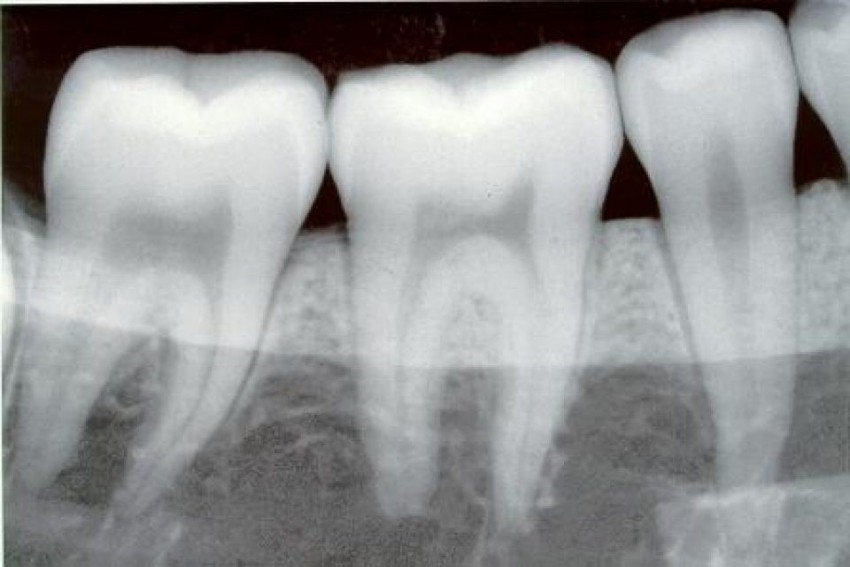

Радиовизиография – это рентген снимок рядом стоящих зубов; важнейший метод диагностики как состояния зубов, так и окружающих их тканей.

- определить глубину кариозного поражения;

- оценить строение корневой системы зуба, длину корневых каналов;

- увидеть трещины в корнях зуба, наличие кист и объем воспалительного процесса;

- обнаружить новообразования и инородные предметы в канале;

- проконтролировать качество пломбировки, удаления зуба, установки имплантата.